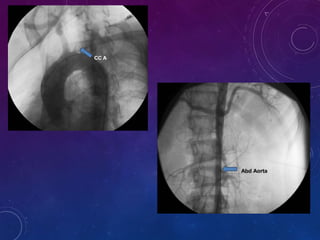

Angiography:

• standard for diagnosis and evaluation of the extent of

disease.

Angiography is used to evaluate only the appearance of the lumen

and cannot be used to differentiate between active and inactive

lesions.